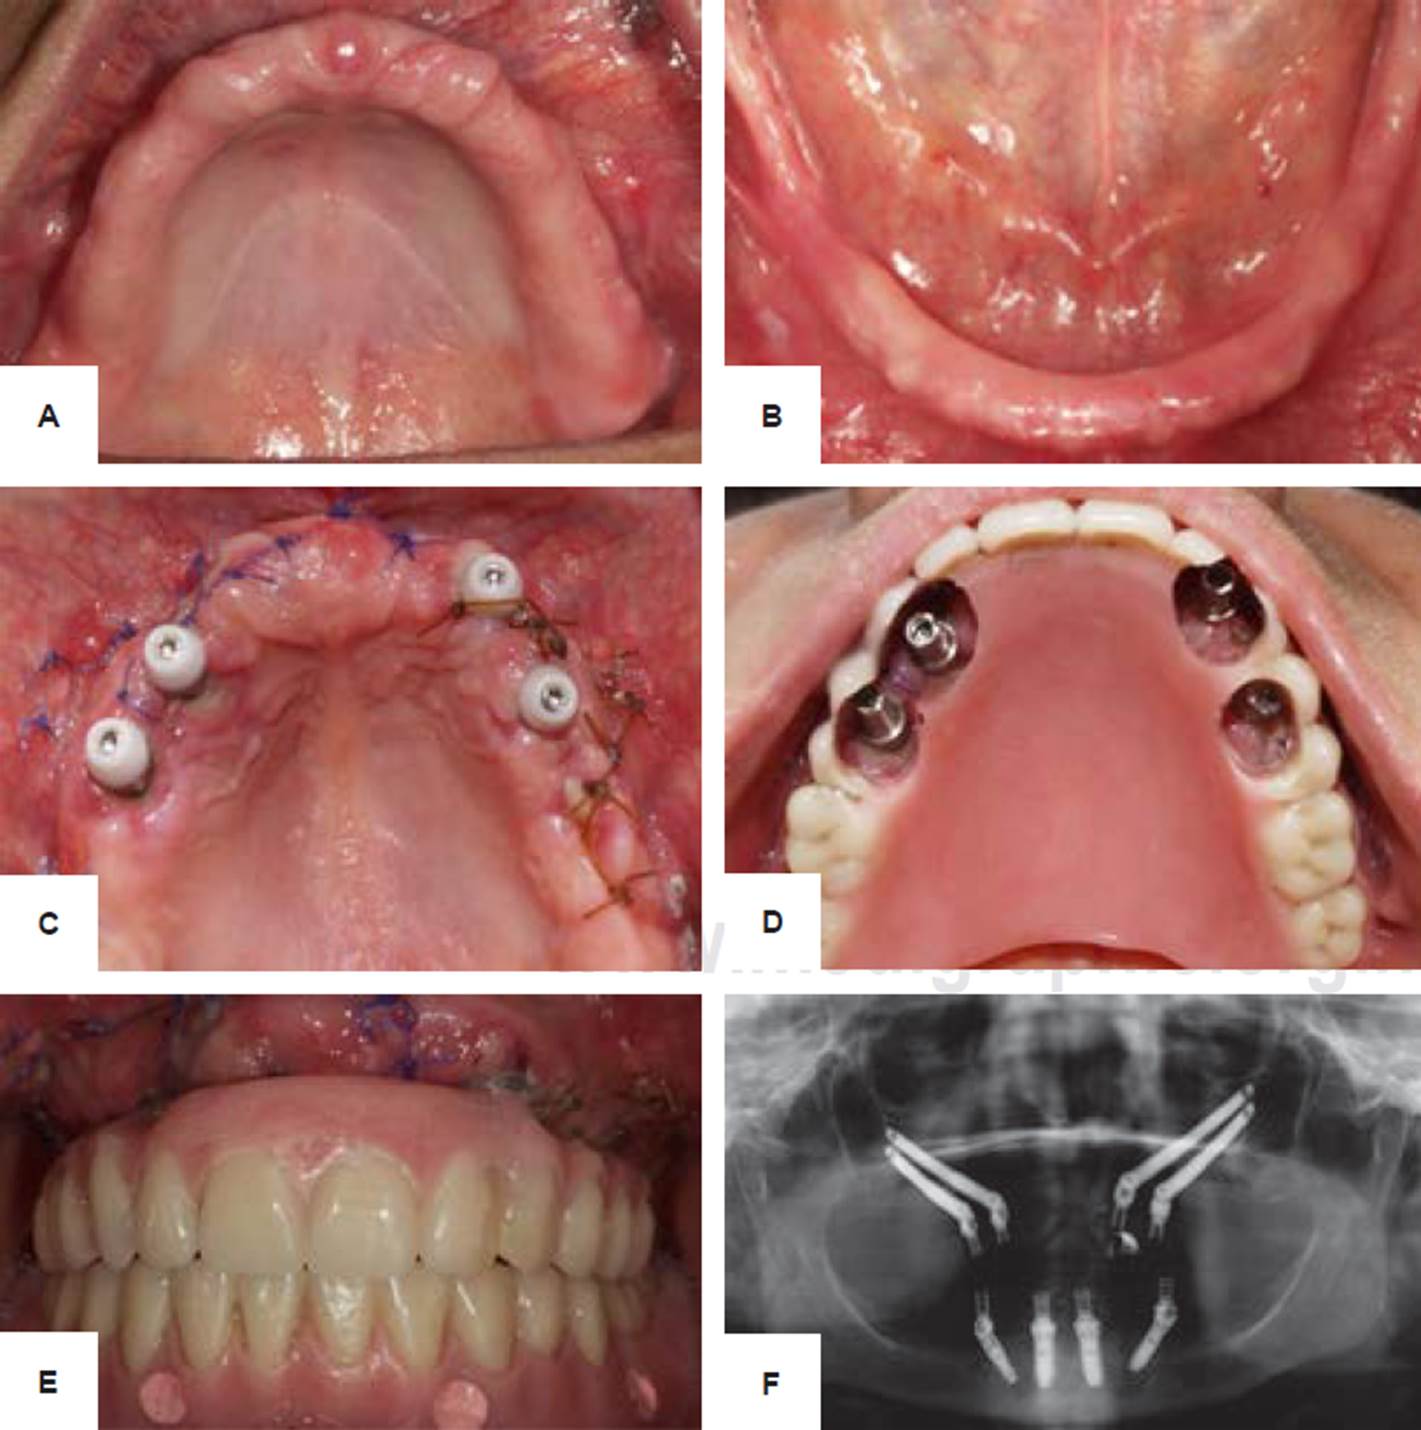

Figura 4 Fotografías intraorales. A) Maxilar inicial. B) Mandíbula inicial. C) Postoperatorio a 10 días. D) Localización de la emergencia de los implantes. Colocación de prótesis provisional atornillada. Ortopantomografía que muestra cuatro implantes cigomáticos y cuatro convencionales All on Four en mandíbula. Fuente directa.

Se colocaron cuatro implantes cigomáticos intrasinusales, mediante incisión linealdeespesortotal, se localizó el agujero y nervio infraorbitario, se diseñó una ventana sinusal y se comenzó el protocolo de fresado, iniciando con una fresa de bola, se colocaron los implantes cigomáticos en los cuales se obtuvo 35 Ncm de torque; posteriormente se colocaron los Multi-Unit y en este caso se decidió dejar la carga inmediata para 10 días posteriores a la cirugía (carga temprana). A los 10 días se presentó la paciente a la clínica y se rehabilitó de forma provisional (Figura 4C-4E). Para complementar su tratamiento en la mandíbula se decidió colocar cuatro implantes (All on Four). En la ortopantomografía se observaron implantes en posición y cumpliendo función (Figura 4F). En el momento de la colocación de la prótesis es considerable el cambio que se observó en el aspecto físico de la paciente (Figura 3B).